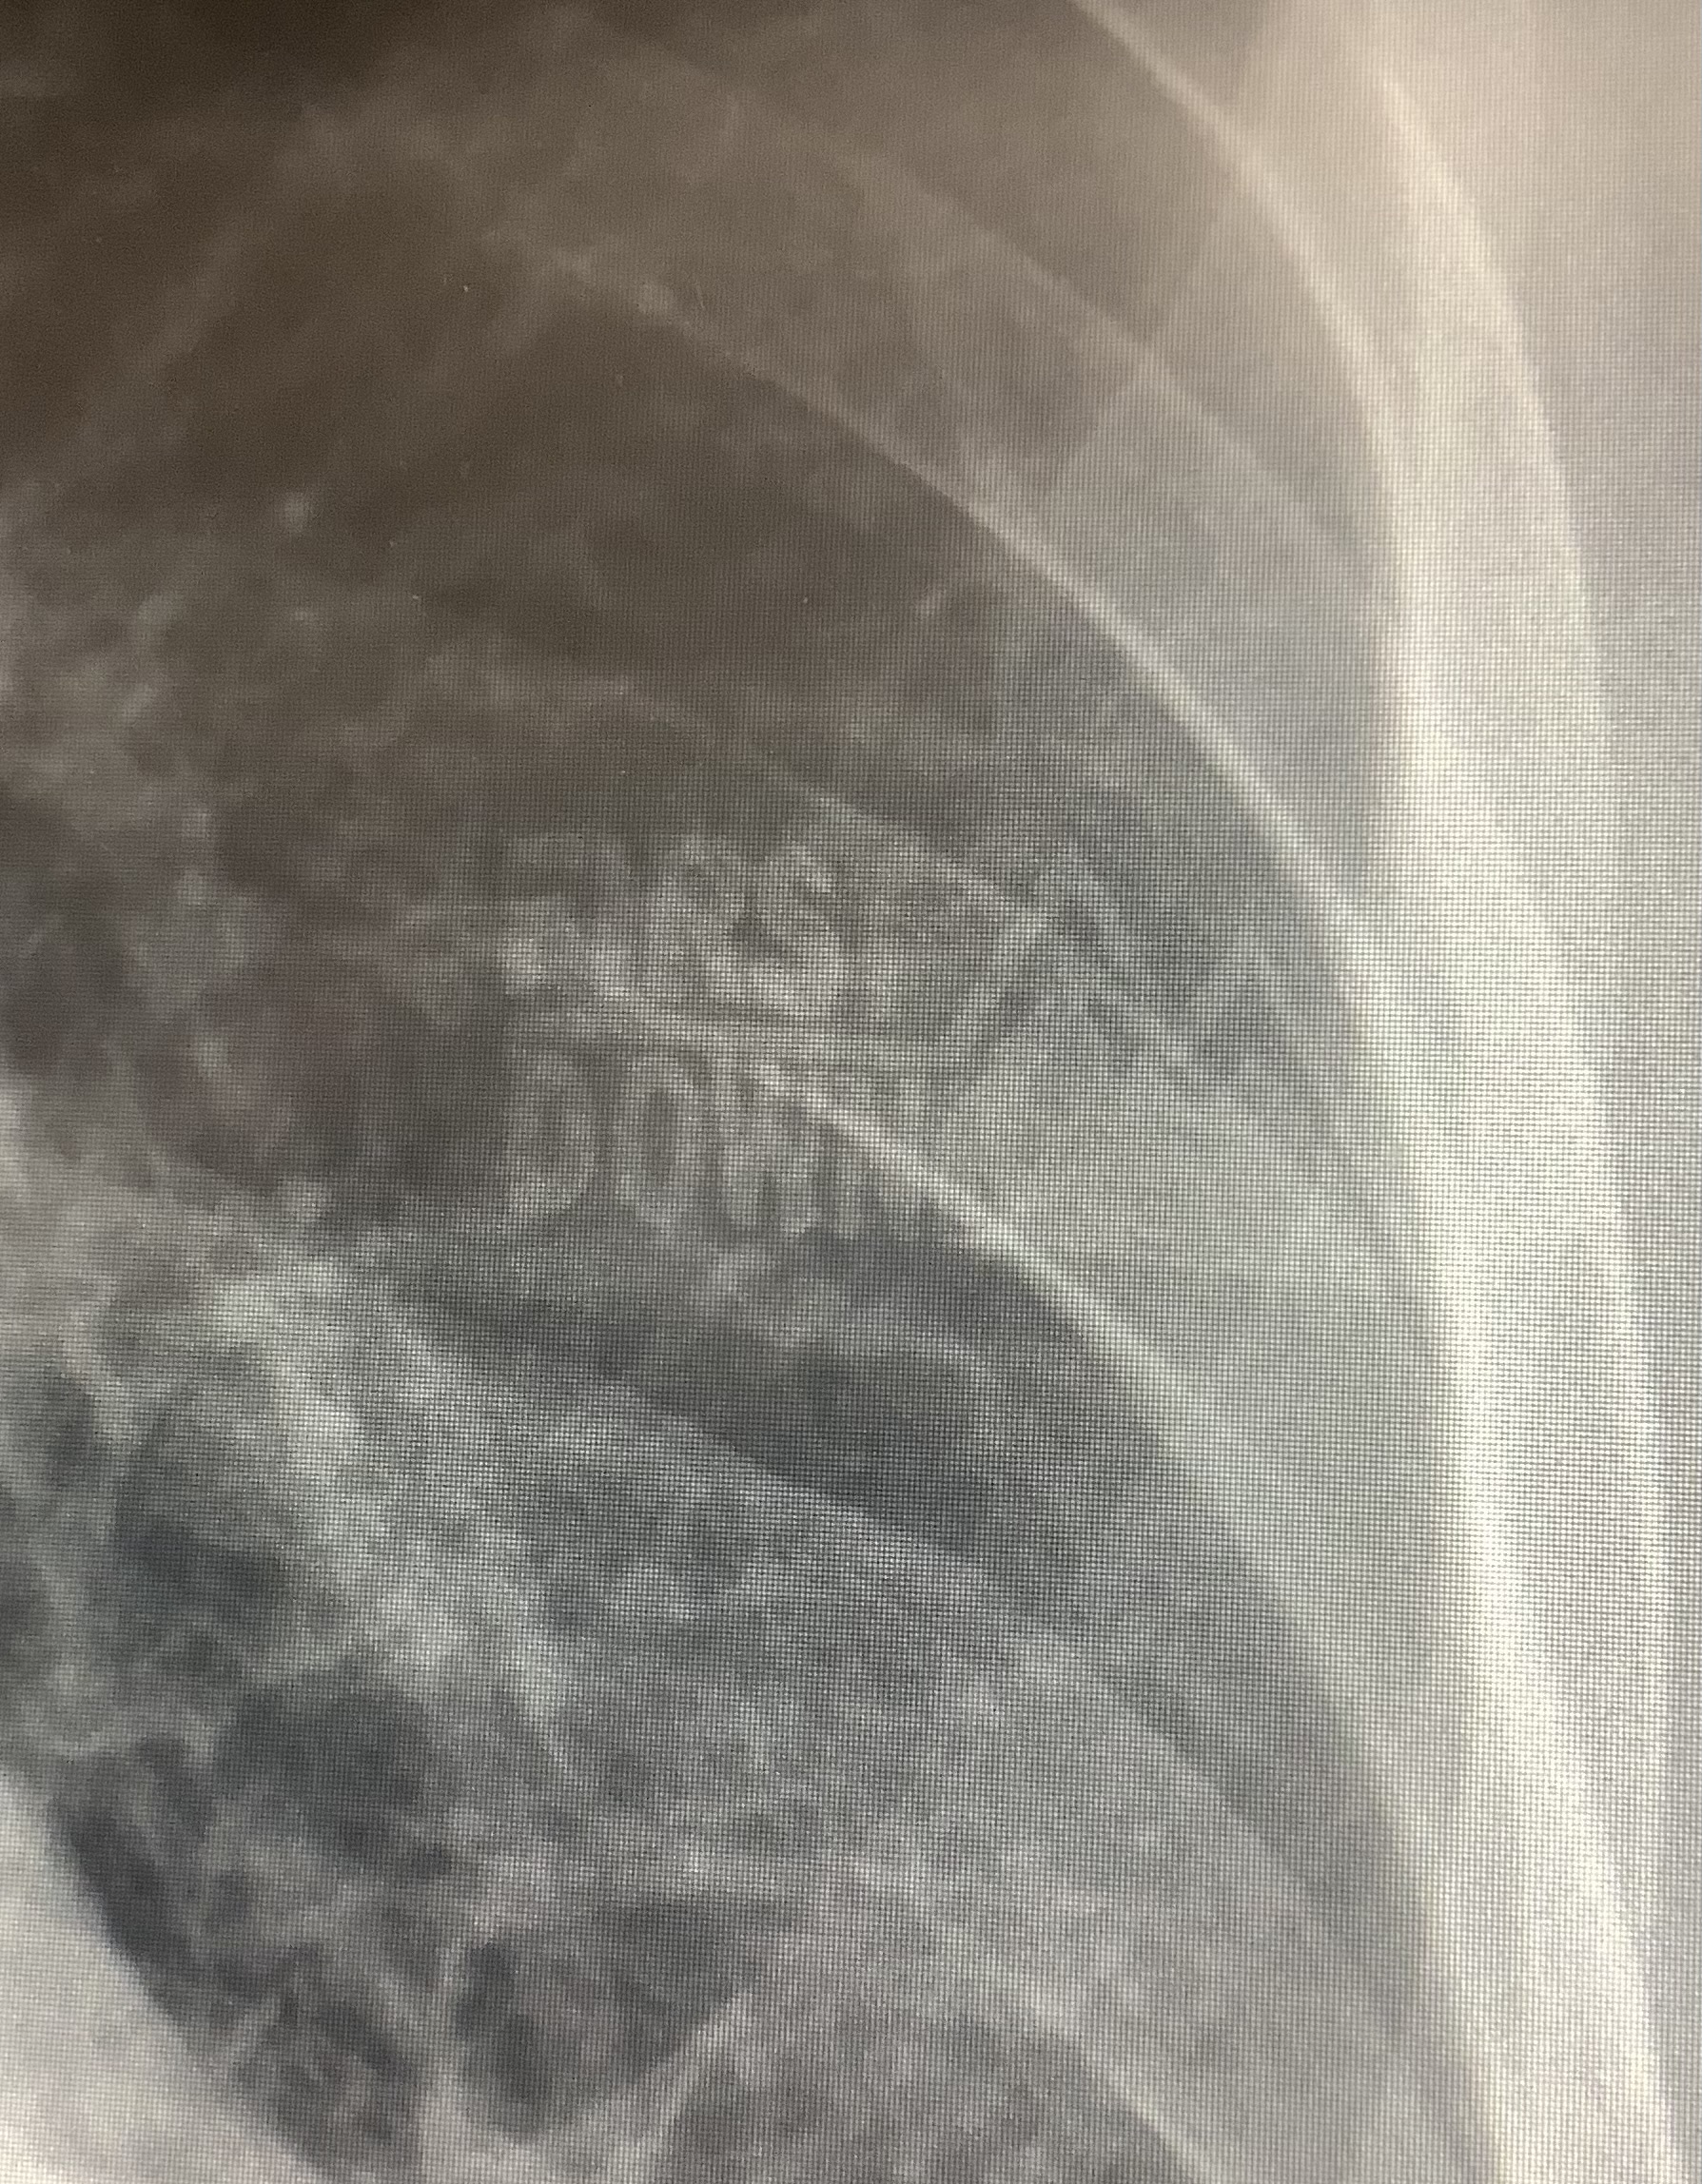

レントゲン 服を脱いで頂く理由

本院の放射線科では、胸部レントゲン撮影前に金具付きの下着やマーク、ボタンのある衣服等を脱いで頂いております。

その理由としましては、撮影した画像に写り、見たい場所や病変と被ってしまい見落としてしまう可能性があるからです。

より良い画像を得るためにもご協力宜しくお願い致します。